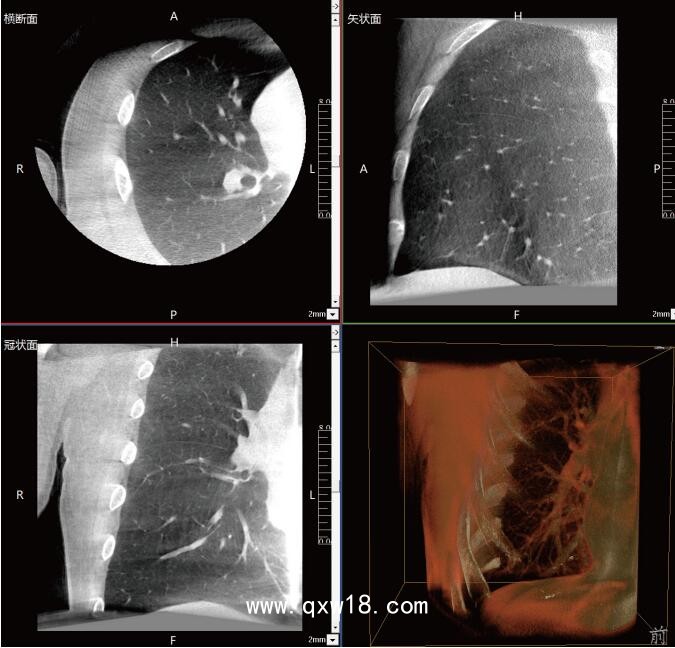

呼吸介入C型臂臨床應用-普愛醫(yī)療三維C型臂CT產(chǎn)品說明:

近年來,在肺部手術領域的應用呈現(xiàn)出顯著的增長態(tài)勢。這一技術不僅滿足了臨床指導穿刺、精準確認病變與針尖位置關系的迫切需求,更通過大量臨床研究的驗證,證明了其在肺結節(jié)診斷、定位及治療中的有效性和安全性。

《中國專家對CBCT引導下肺結節(jié)的診斷、定位和治療的共識》提到C型臂CT系統(tǒng)憑借其強大的功能,能夠充分滿足透視監(jiān)測、病變與工具位置確認、消融區(qū)監(jiān)測以及并發(fā)癥檢查等多元化的臨床需求。因此,在考慮設施條件(如導航設備、手術室空間)、靶病灶特性(大小、密度)、麻醉方法及干預路徑(經(jīng)支氣管或經(jīng)胸)等多重因素的基礎上,C型臂CT系統(tǒng)成為了眾多醫(yī)療機構的優(yōu)選方案。

呼吸介入C型臂CT的臨床適應癥廣泛,包括支氣管鏡檢查、肺結節(jié)穿刺活檢、肺結節(jié)定位、肺結節(jié)消融以及經(jīng)支氣管肺結節(jié)診療等多個領域。其臨床應用價值不言而喻:在經(jīng)支氣管干預肺結節(jié)時,透視功能可精準引導支氣管鏡與活檢鉗直達靶結節(jié);重建的三維圖像則能清晰展示干預工具的位置,確保操作的準確性。在肺結節(jié)消融過程中,呼吸介入C型臂CT更是實現(xiàn)了高精度定位,有效提升了治療效果。